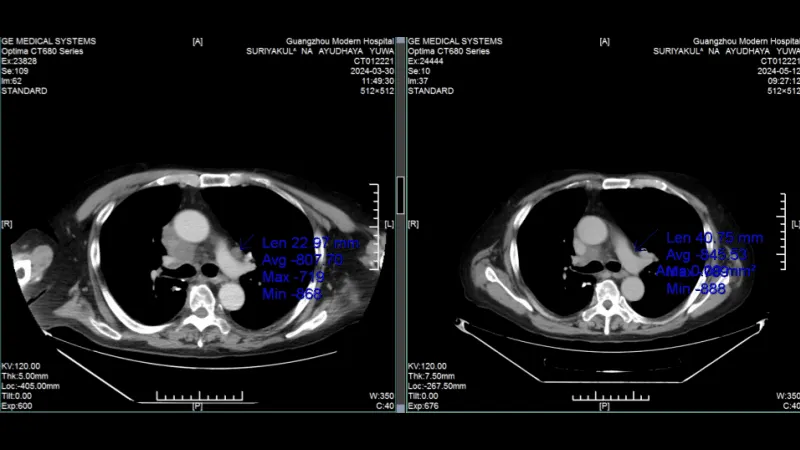

КТ-снимки подтвердили: опухоль в легком практически исчезла

КТ-снимки подтвердили: динамика положительная, болезнь отступает

26 февраля 2024 года результаты КТ показали, что опухоль легкого значительно уменьшилась